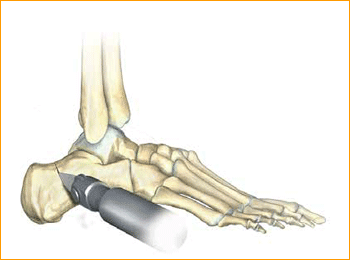

6. SELECT SCREW SIZE

Place the soft tissue guide (the guide should be used throughout) over the guide wire and open the near cortex using the appropriate cannulated profile drill.

7. SOFT TISSUE GUIDE

Place the soft tissue guide over the guide wire and open the near cortex using the appropriate cannulated profile drill.

Tip: Drills should be advanced slowly with continuous irrigation to minimize the potential of heat build-up. Clean drill periodically during each procedure to optimize performance.

8. DRILL

Leaving the soft tissue guide in place, drill into the far fragment with the appropriate cannulated, long profile drill. Reference the markings on the drill to confirm desired depth.